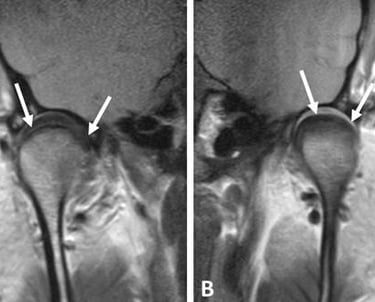

La resonancia magnética proporciona imágenes detalladas de los tejidos blandos, permitiendo evaluar el disco articular, los ligamentos y los músculos asociados a la ATM.

Evaluación mediante resonancia magnética de la ATM